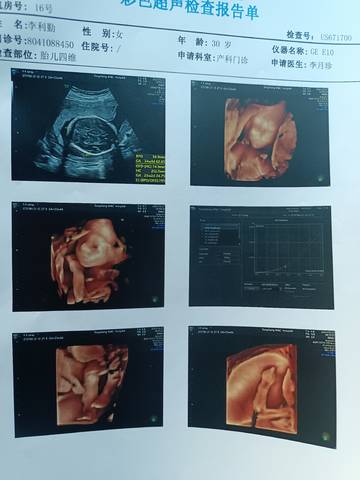

四维出来了,谁能看出来是男孩还是女孩呀?

甜美的可爱 2021-12-28 12:14

医生能看出

可爱的孕妈,我们都是一样觉得好奇,确实没什么依据,就个惊喜给自己吧,一切顺利!

你好亲爱的,通过这个来判断男孩女孩是不太准确的哈,我们要给他同等的关爱和呵护,也祝你可以如愿以偿,心想事成。